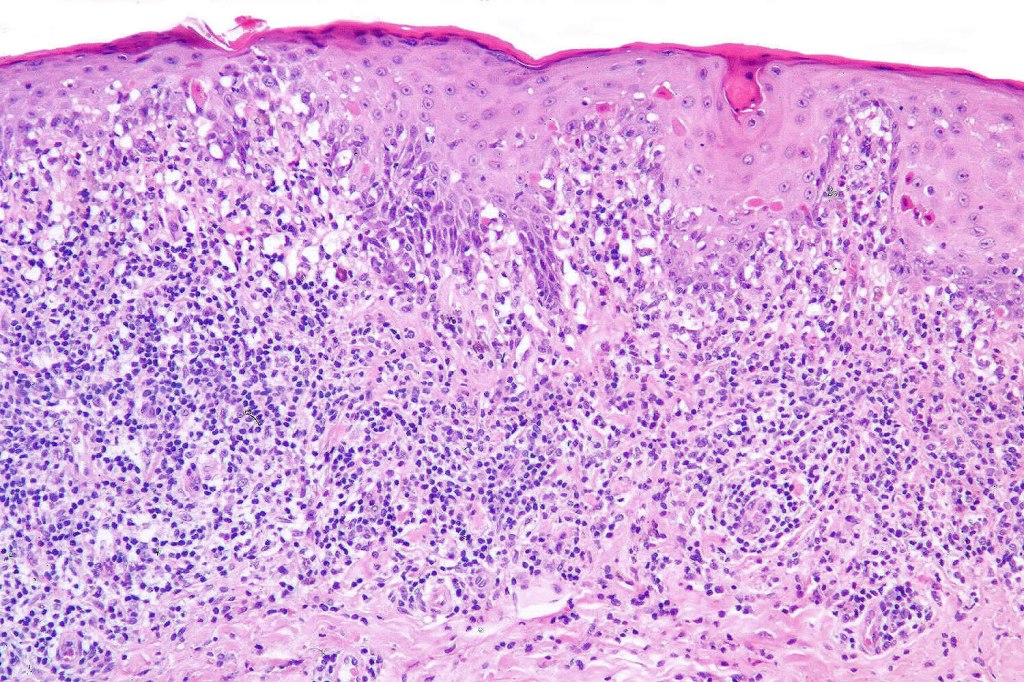

Histological features

•Hyperkeratosis +/- parakeratosis

•Wedge-shaped hypergranulosis

•Generally irregular (sometimes saw-tooth) acanthosis but may show broad acanthosis

•Interface change

•Conspicuous cytoid bodies

•Pigment incontinence

•Band-like or perivascular infiltrate of lymphocytes, histiocytes with occasional eosinophils & plasma cells